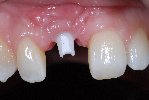

- Komplette Regeneration der Pappille 3 Monate nach der Eingliederung der Implantatkrone

- Vollkeramische Restauration auf Implantat